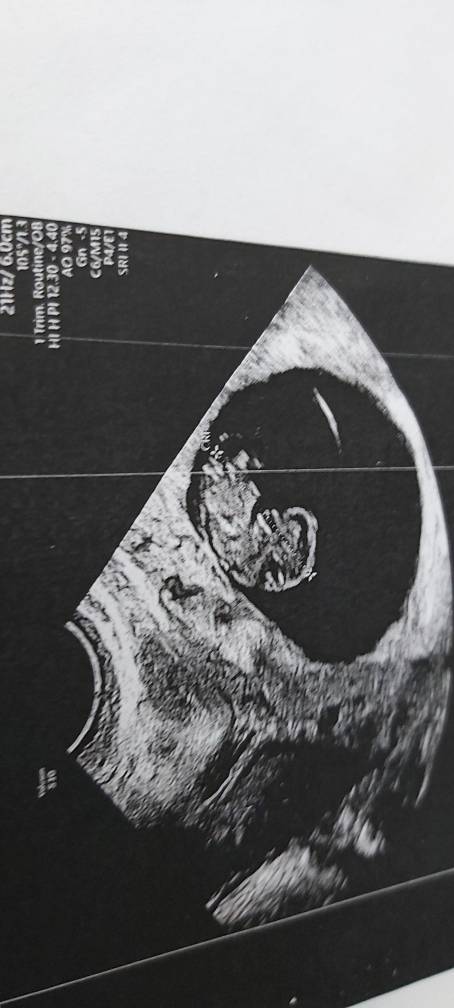

U mnie zdjęcie z piątku już widać małego człowieczka [emoji16]

20191101_122146.jpeg